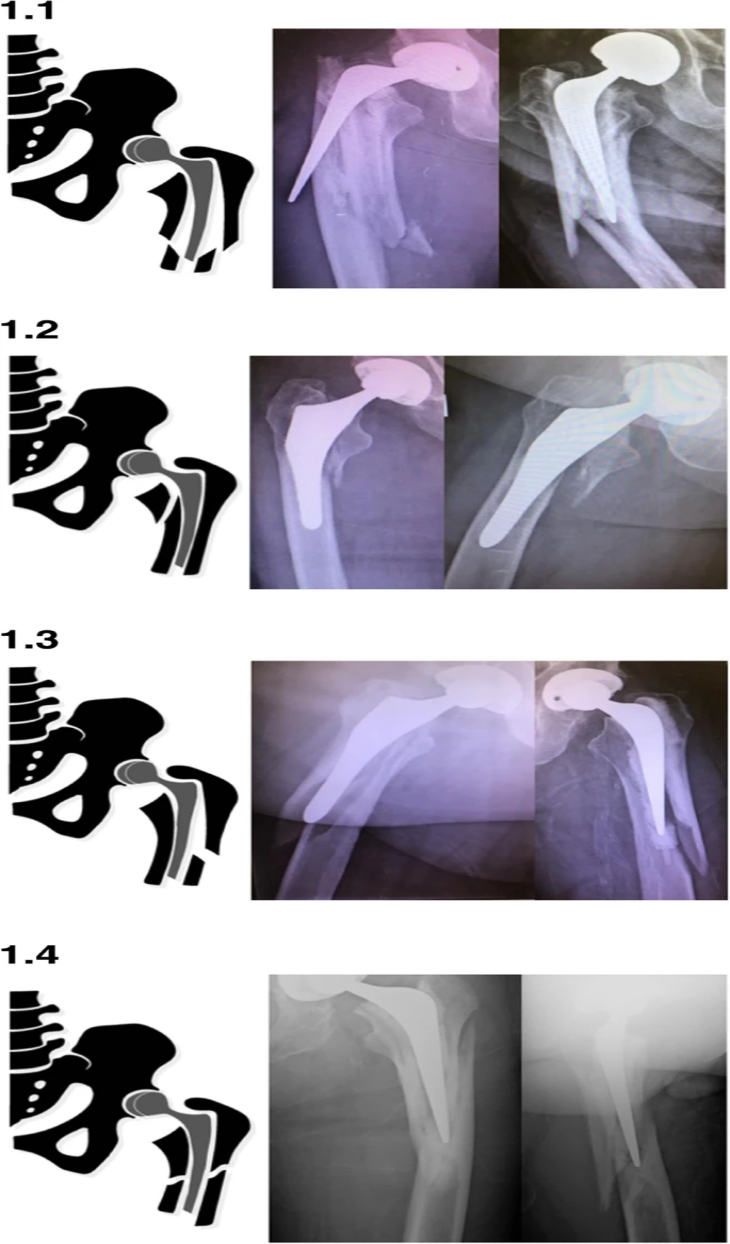

1. Переломы VancouverB2 подразделяются на четыре различных типа переломов: ранее описанный оскольчатый «взрывной», грейферный и спиральный, а также недавно наблюдаемый «обратный» грейферный.Представлен репрезентативный рентгеновский вид серии и соответствующее графическое изображение (рис. 1).

2. Взрывные и спиральные переломы были в значительной степени связаны с цементированными ножками, тогда как переломы лоскута были в значительной степени связаны с нецементированными ножками.

3. Обратная раскладушка произошла одинаково в обоих стеблях.

4. Связь подтипов Ванкуверской классификации, включая четыре типа переломов B2, описанных выше, с геометрией ножки отражает общую тенденцию типов переломов.

Перелом Ванкувера B2